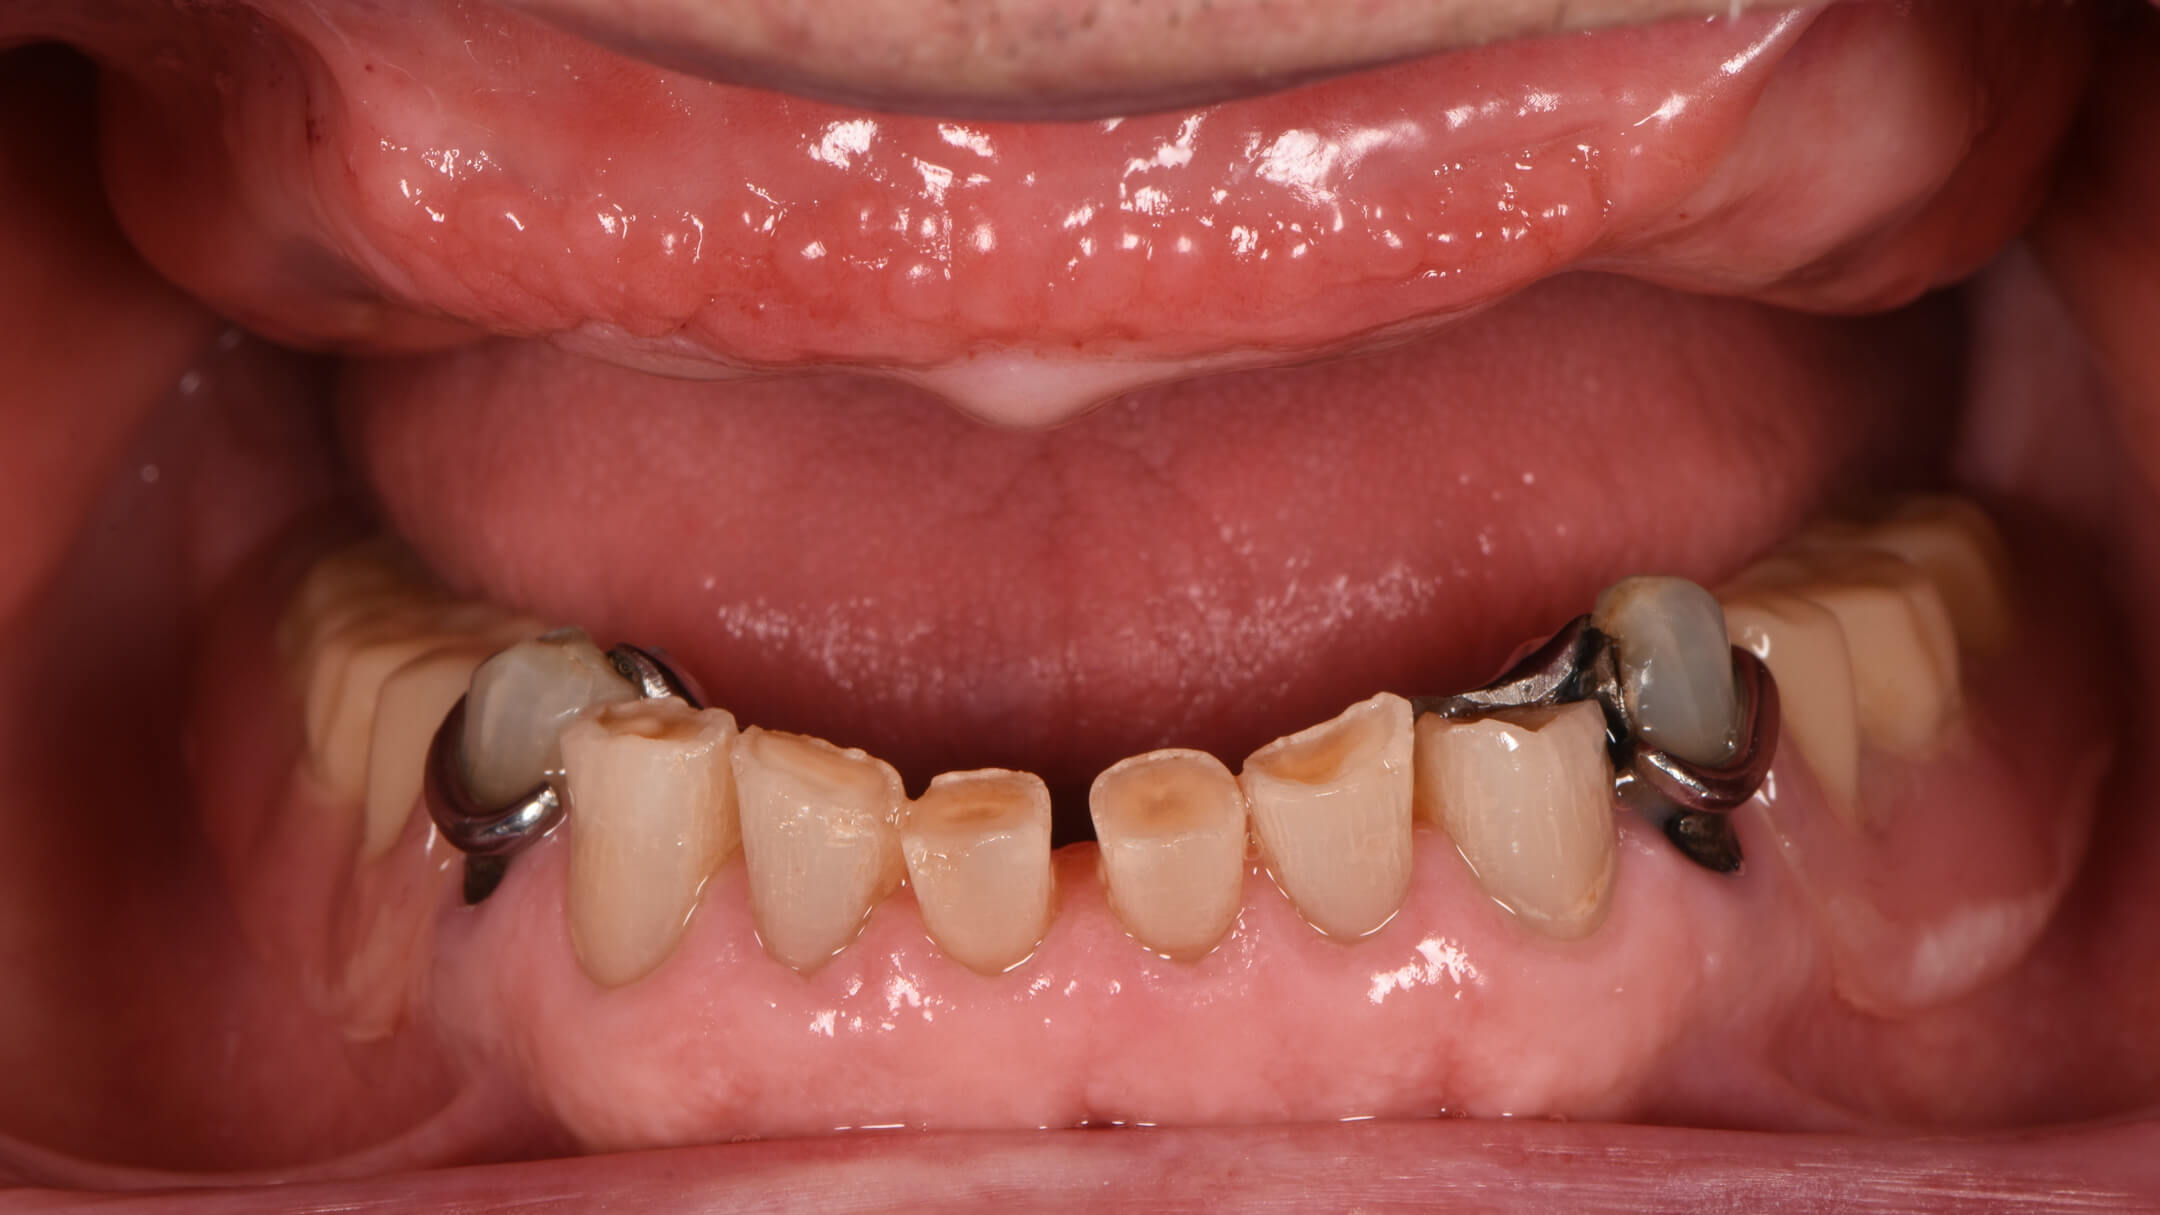

Dental Implants

Before